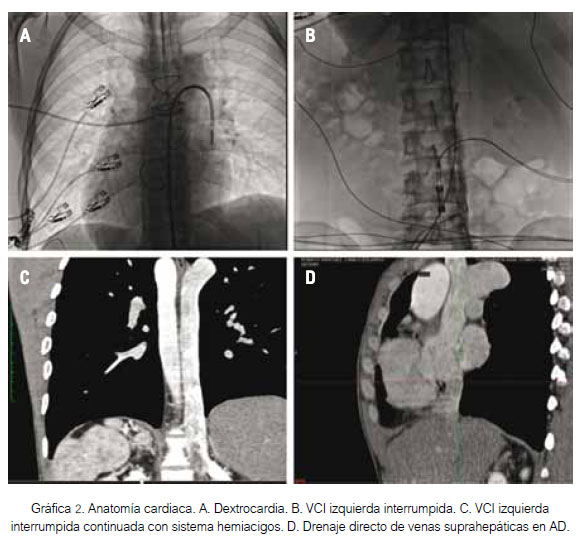

Se realizó ablación del FlA empleando sistema de mapeo tridimensional (NavX; St Jude Medical, Inc.). Se practicó venografía desde las venas ilíacas para observar la vena cava inferior izquierda, interrumpida a nivel de la vena renal derecha y continua con el sistema venoso hemiácigos, para llegar a la vena cava superior que drena en la AD (gráfica 2). Se realizó reconstrucción tridimensional de AD con un catéter circular (Inquiry AFocus II, St Jude Medical, Inc), así como mapa de voltaje con áreas de cicatriz en segmento inferior de pared lateral de AD, el cual corresponde a atriotomía. Además, se observó área de cicatriz en el tercio inferior del séptum interauricular, que corresponde al parche del cierre de CIA (gráfica 3A).

El electrocardiograma (gráfica 1) mostró ritmo de flúter auricular. El ecocardiograma documentó situs inversus, fracción de eyección del ventrículo izquierdo de 38%, sin shunt residual. La tomografía axial computarizada tuvo hallazgos compatibles con situs inversus e isomerismo izquierdo (ausencia de segmento hepático de la vena cava inferior izquierda, ambos pulmones bilobulados y poliesplenia), conexión de venas suprahepáticas y vena cava superior a la aurícula derecha (AD).